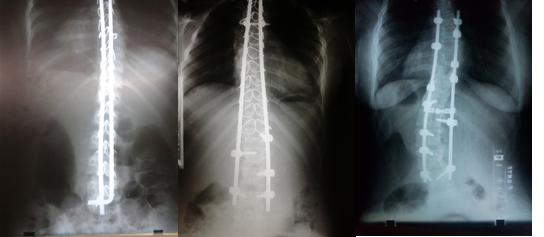

En el grupo A se realizaron tres técnicas diferentes en 31 pacientes, a 11 pacientes se les realizó la técnica clásica de Luque con alambrado sublaminar, en 15 pacientes el sistema híbrido con tornillos pedicular y alambrado sublaminar y a 5 pacientes se les realizó fijación con tornillos pediculares completo. (Fig. 2).

A los pacientes del grupo B se les realizó la técnica modificada por el autor de este trabajo, con una casuística de 19 pacientes. (Figura 3)

Se realiza un abordaje posterior de la columna vertebral, se esqueletizan apófisis espinosas, láminas, articulares y transversas a ambos lados, se liberan las partes blandas, para hacer más flexible la curva y lograr mayor corrección. Se colocan tornillos pediculares en la vértebra final inferior bilateral, en el lado cóncavo en la inmediata superior y en el lado convexo se deja una vértebra por medio. (Figura 1).

En el lado convexo, se colocan tornillos corticales de 4,5 mm a nivel del ápex de la curva. Si el ápex es una vértebra, se colocan tres tornillos uno a nivel del ápex y uno en las vértebras adyacentes superior e inferior; si el ápex es un disco, se colocan tornillos corticales en las vértebras adyacentes a este. En el lado cóncavo, en las vértebras que se les colocó tornillo cortical, se utilizan alambres sublaminares dobles de 1,2 mm. En el resto de las vértebras se colocan alambres sublaminares simples de 1,2 mm a ambos lados y dobles en la vértebra final superior. (Figura 1).

Se coloca primero la barra del lado cóncavo; se une a los tornillos pediculares y alambres, amoldada a la curva, luego se realiza la desrotación y corrección en el plano coronal y sagital. Se fijan los tornillos pediculares de ese lado y se aprietan los alambres sublaminares. Seguidamente se coloca la barra del lado convexo, por fuera de los tornillos corticales, se fijan alambres sublaminares y tornillos pediculares.